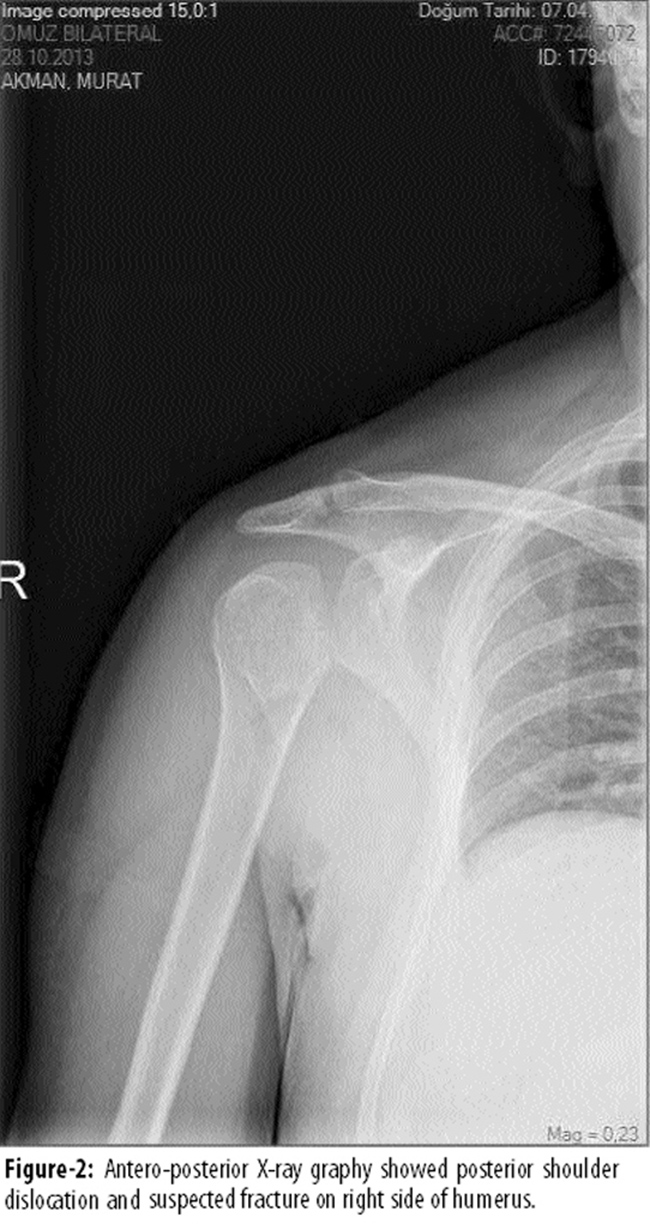

There was a suspected fracture line on the right side (Figure-2).

To confirm the suspected fracture on right side, an axial computerized tomography was performed. It revealed both fracture and dislocation of the humeral head. The patient was referred to the department of orthopaedics and traumatology for surgery.